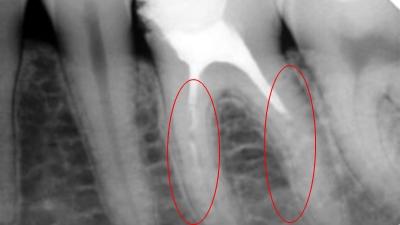

Каналы закрылись не полностью

В таком случае пломбировочный материал не выходит за пределы, а закрывает канал не полностью из-за того, что его просто недостаточно. Необработанная полость становится очагом развития инфекции, возникает воспалительный процесс, вызывающий болевые ощущения. В этом случае ошибка врача заключается в неверной оценке длины каналов или равнодушии к неудовлетворительным результатам, ведь как упоминалось ранее, приборы способны показать, появились ли недочёты после операции.

Лечение заключается в распломбировании канала, чистке, снятии воспаления и проведении процедуры пломбировки заново.